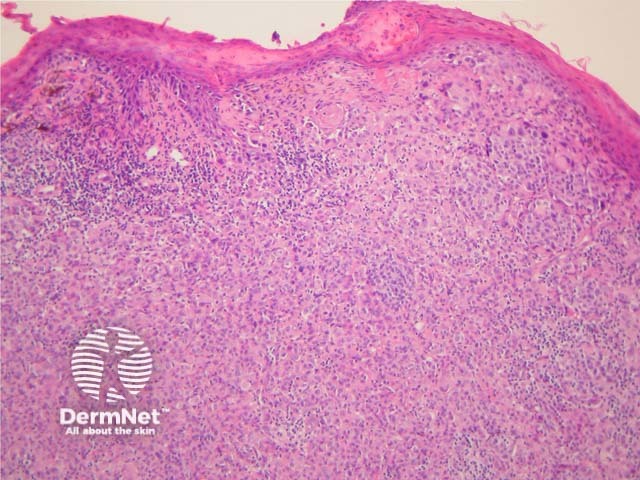

Figure 3